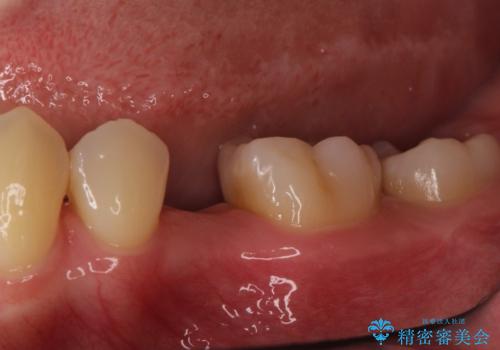

小臼歯のインプラント

- 20代女性

- 小臼歯が先天性欠損していたため、インプラントにて補綴しています。